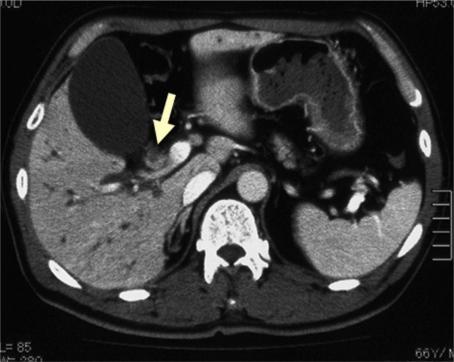

We herein report a rare case of squamous cell carcinoma of the hilar bile duct. A 66-year-old Japanese male patient was admitted to our hospital because of appetite loss and jaundice. Abdominal computed tomography revealed an enhanced mass measuring 10 × 30 mm in the hilar bile duct region. After undergoing biliary drainage, the patient underwent extended right hepatic lobectomy with regional lymph nodes dissection. The tumor had invaded the right portal vein. Therefore, we also performed resection and reconstruction of the portal vein. Histopathologically, the carcinoma cells exhibited a solid structure with differentiation to squamous cell carcinoma with keratinization and intercellular bridges. Immunohistochemical staining of the tumor cells revealed positive cytokeratin staining and negative CAM 5.2 staining. Based on these findings, a definitive diagnosis of well-differentiated squamous cell carcinoma of the hilar bile duct was made.

我们在此报告一例罕见的肝门部胆管鳞状细胞癌病例。一名66岁的日本男性患者因食欲减退和黄疸入院。腹部计算机断层扫描显示肝门部胆管区域有一个大小为10×30毫米的强化肿块。在进行胆道引流后,患者接受了扩大右肝叶切除术并进行区域淋巴结清扫。肿瘤侵犯了右门静脉。因此,我们还进行了门静脉切除和重建。组织病理学检查显示,癌细胞呈实体结构,分化为伴有角化和细胞间桥的鳞状细胞癌。肿瘤细胞的免疫组织化学染色显示细胞角蛋白染色阳性,CAM 5.2染色阴性。基于这些发现,确诊为肝门部胆管高分化鳞状细胞癌。